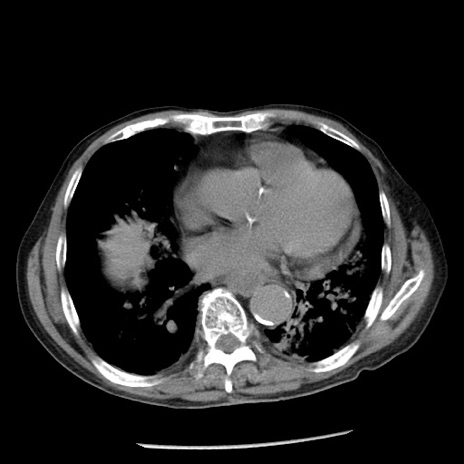

症例26(横断像)

冠状断像

【症例】80歳代男性

【主訴】嘔吐

【現病歴】昨晩2回嘔吐あり、今朝になっても嘔吐あり。来院。

【既往歴】胃潰瘍

【身体所見】意識清明、BT 37.6℃、BP 166/95mmHg、HR 100bpm、SpO2 97%、腹部:平坦・軟、腸蠕動音聴取良好、圧痛なし。

【データ】WBC 21900、CRP 1.46